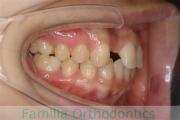

No.22V-449

- 主な症状:

- 上顎前突

- その他の症状:

- 叢生

- 年齢:

- 14歳

- 性別:

- 男性

- 抜歯部位

- 上:

- 44

- 下:

- 8448

- 主な使用装置:

- FEA

- 治療にかかった費用:

- 87万円

歯並びをきれいにしたいということで来院されました。上下左右から小臼歯を抜歯して、マルチブラケット法を行っています。2年弱、25回程度の通院が必要でした。

かなり強い叢生(でこぼこ、凹凸、ガタガタ)ですので、保定をしっかりしないと後戻りのリスクがあります。

- ≫治療前

-

上顎

下顎

前歯の関係など

右側

正面

左側

- ≫治療後